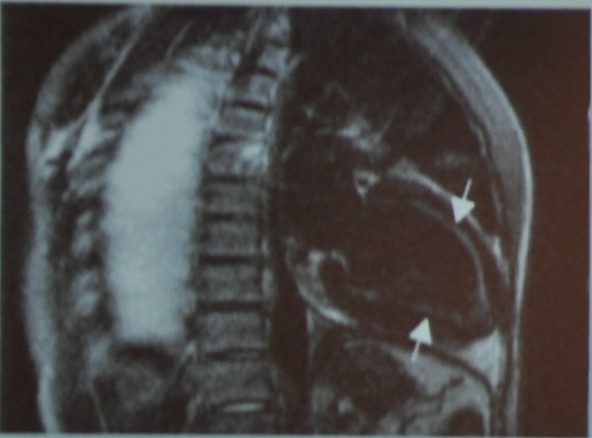

图13 MR成像

患者的心脏收缩功能是完全正常的,但是心包及其肥厚(1cm),从上图中各种成像中都能看到心包像个壳一样包住了心脏,而且心包弥散性纤维化伴局部钙化。

该患者最终被诊断为缩窄性心包炎,紧接着做了心包剥离术。